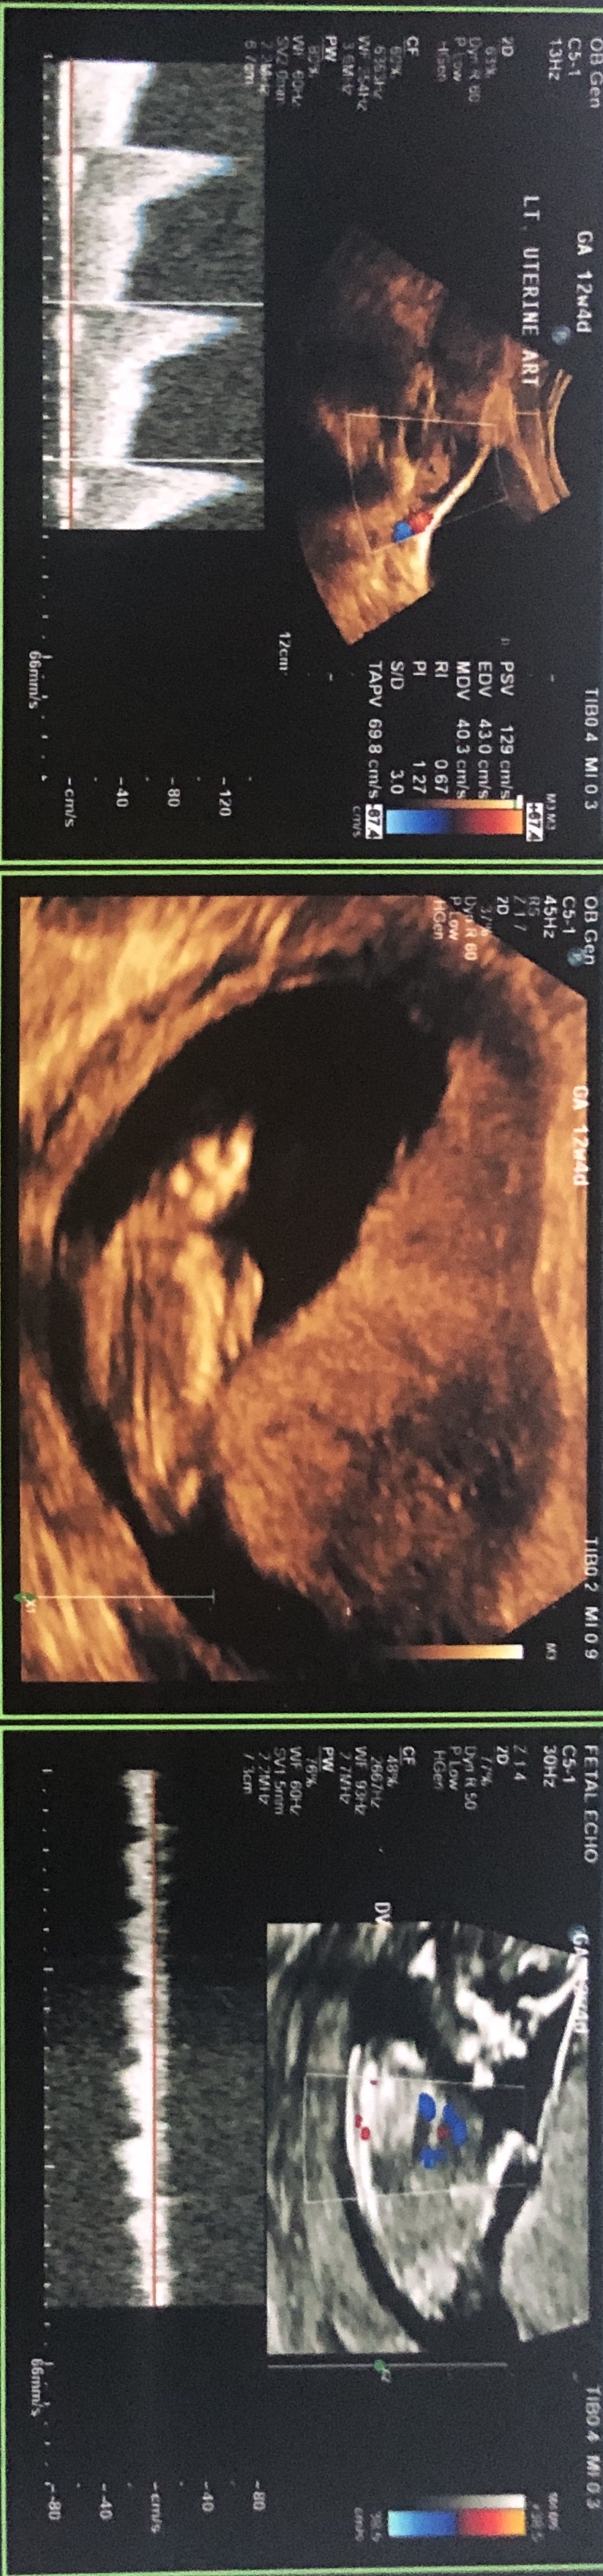

Little anxious to find our little one’s gender. Attached are ultrasound images at 12+4 days (age as per CRL dating)Attachment 42397Attachment 42398Attachment 42397Attachment 42398